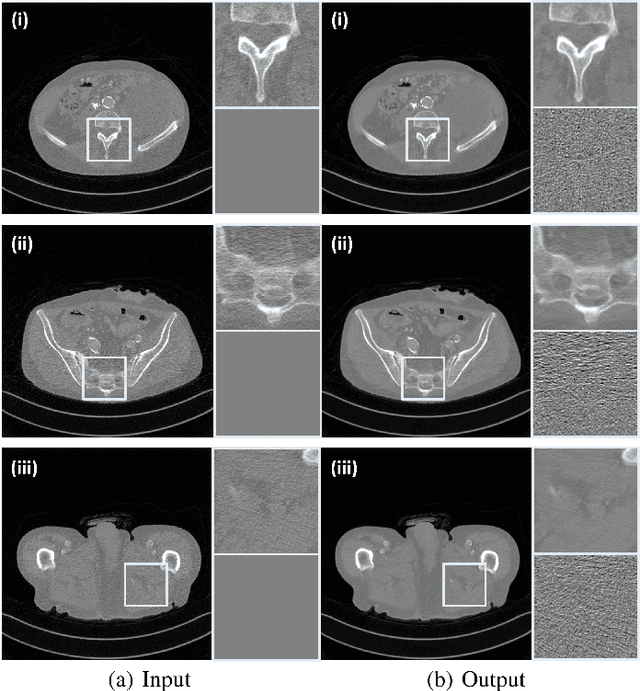

Recently, CycleGAN was shown to provide high-performance, ultra-fast denoising for low-dose X-ray computed tomography (CT) without the need for a paired training dataset. Although this was possible thanks to cycle consistency, CycleGAN requires two generators and two discriminators to enforce cycle consistency, demanding significant GPU resources and technical skills for training. A recent proposal of tunable CycleGAN with Adaptive Instance Normalization (AdaIN) alleviates the problem in part by using a single generator. However, two discriminators and an additional AdaIN code generator are still required for training. To solve this problem, here we present a novel cycle-free Cycle-GAN architecture, which consists of a single generator and a discriminator but still guarantees cycle consistency. The main innovation comes from the observation that the use of an invertible generator automatically fulfills the cycle consistency condition and eliminates the additional discriminator in the CycleGAN formulation. To make the invertible generator more effective, our network is implemented in the wavelet residual domain. Extensive experiments using various levels of low-dose CT images confirm that our method can significantly improve denoising performance using only 10% of learnable parameters and faster training time compared to the conventional CycleGAN.